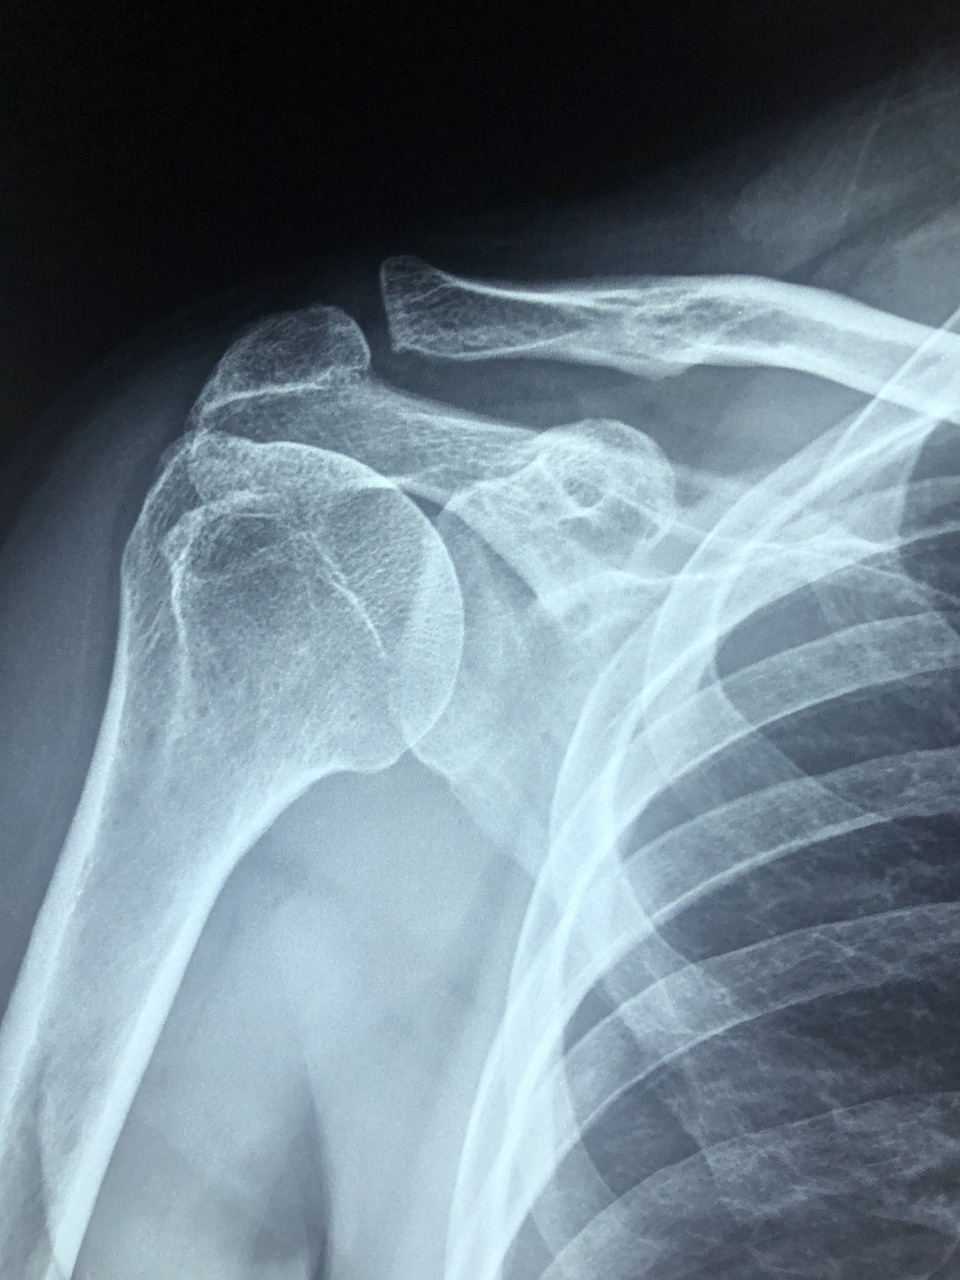

스테로이드 주사는 몸속 염증 반응을 강하게 억제하는 약물로, 어깨 관절이나 근육 주변에 직접 주입하여 통증을 줄여주는 치료법입니다. 특히 회전근개 파열, 유착성 관절낭염(오십견), 석회화건염 등 염증이 주된 질환에 빠른 진통 효과를 제공합니다.

또한, 통증이 갑자기 심해졌다면 단순 염증이 아니라 **파열** 가능성도 있으니, MRI 등의 정밀검사를 먼저 진행하는 것이 우선입니다.